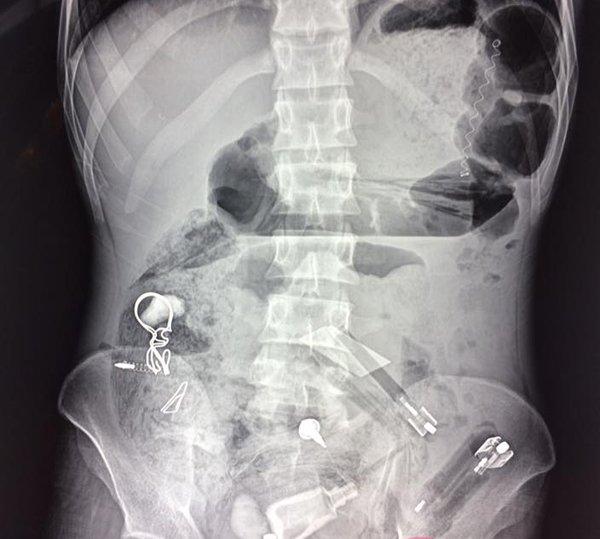

Kết quả chụp X-quang cho thấy, trong dạ dày bệnh nhân có rất nhiều dị vật với các hình dạng khác nhau, đâm thủng cả ruột.

Ảnh chụp X-quang phát hiện nhiều dị vật trong bụng bệnh nhân